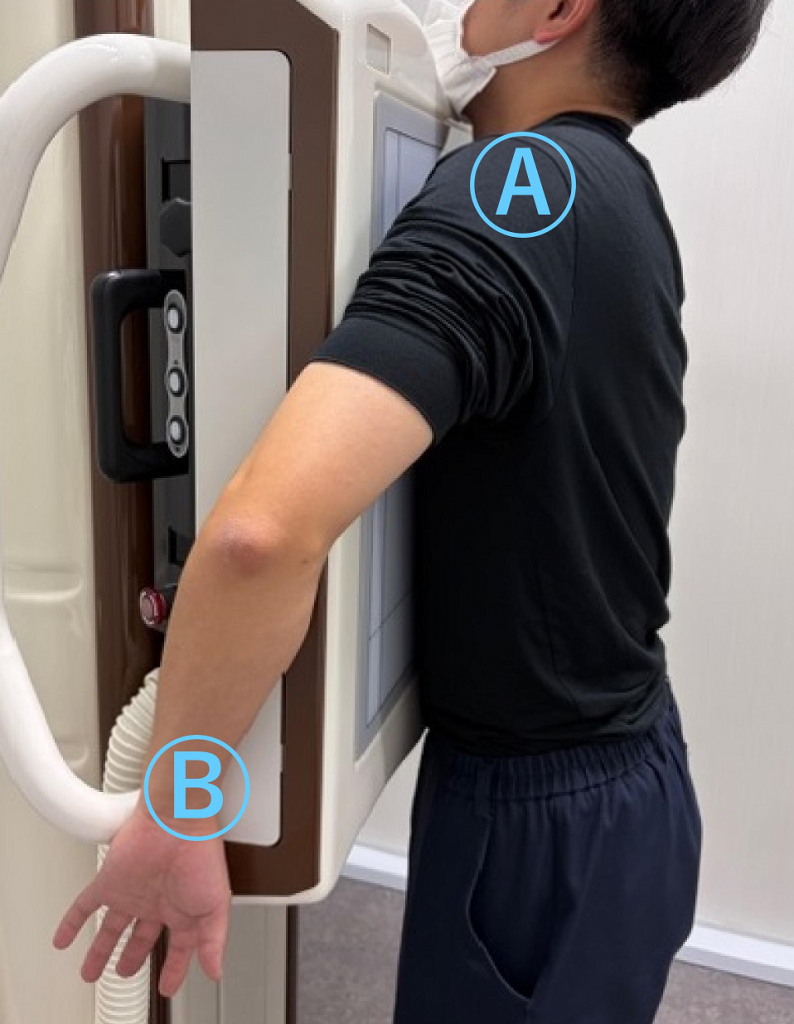

応用編 手を装置の横へ伸ばし、手のひらを外側にむける

Ⓐ肩はできる限り装置に近づける

Ⓑ手のひらを外側に向けることで、

肩甲骨が肺と重ならない姿勢になります